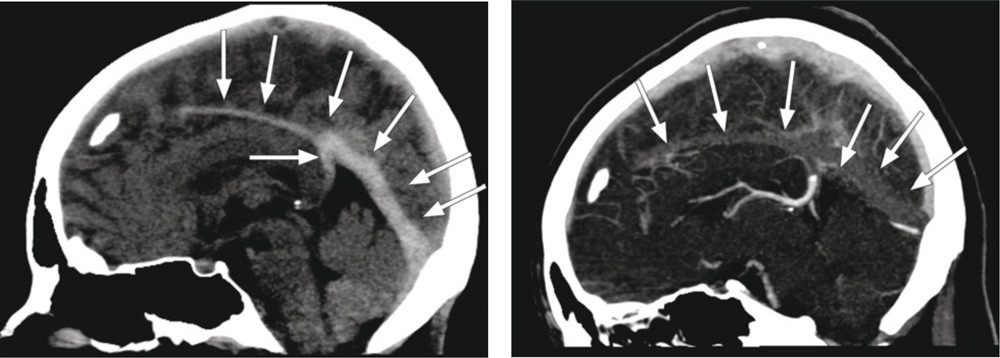

Biokjemiske prøver viste forhøyet D-dimer 0,78 mg/l (0,0 – 0,4 mg/l). Cerebral CT viste forstørret og hyperdens sinus sagittalis inferior, sinus rectus og vena Galeni (bildet til venstre). Funnet ga sterk mistanke om cerebral sinusvenetrombose. Dette ble bekreftet ved kontrastforsterket CT-venografi, hvor man kunne se manglende kontrastfylling av de samme strukturene (bildet til høyre). Antikonsepsjonmidlet ble seponert og pasienten behandlet med lavmolekylært heparin og warfarin. Etter seks måneders behandling viste MR-undersøkelse kun sparsomme resttromber.

Kontrastforsterket CT-undersøkelse kan avdekke «empty delta (Δ) sign», der tromben ses som en lavtett triangulær forandring omgitt av den røntgentette hvite kontrasten. Hos vår pasient så man altså høy tetthet allerede på native serier. Dette fenomenet omtales i litteraturen som «cord sign» og skyldes trombose (2). Et tilsvarende fenomen, kalt «hyperdense artery sign», kan ses ved akutt iskemisk hjerneslag.